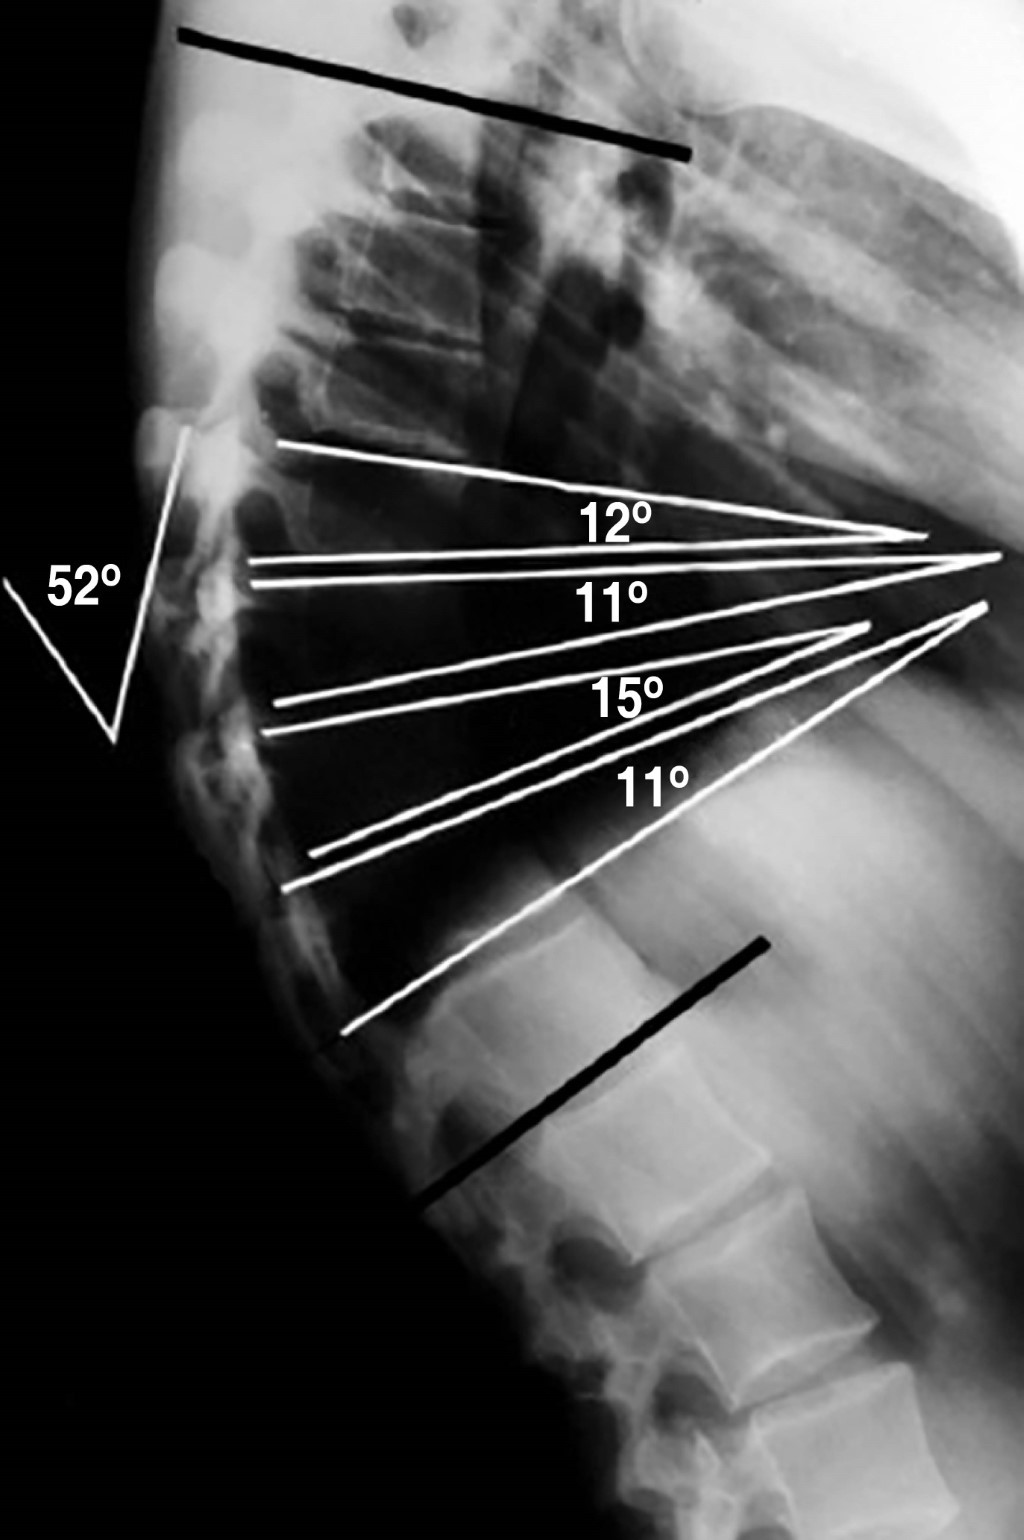

- 2. Acuñamiento vertebral anterior > 5°: este ángulo lo mediremos en la radiografía lateral (al igual que el anterior) trazando dos líneas paralelas a los platillos de la vértebra en cuestión.

- 3. Acuñamiento presente en al menos tres o más vértebras contiguas.2

Debe realizarse una radiografía de columna en proyección lateral con el paciente de pie y con los hombros y brazos en 90°, o sobre la clavícula ipsilateral (en posición clavicular). Para la medición del ángulo de cifosis, se seleccionan las vértebras finales craneal y caudal incluidas en la deformidad. La medida del grado de acuñamiento se obtiene del ángulo de intersección de las tangentes sobre los platillos superior e inferior de cada cuerpo vertebral.9 El criterio diagnóstico establece un acuñamiento superior a los 5° en al menos tres vertebras consecutivas en el ápex de la cifosis (Figura 2).1 También son hallazgos comunes en la radiología la presencia de nódulos de Schmorl, la irregularidad y el adelgazamiento de los platillos vertebrales y el pinzamiento del espacio discal. Para la medición del grado de flexibilidad de la hipercifosis se emplea la proyección lateral con el paciente en hiperextensión sobre una cuña o pivote (Figura 3).1 En la enfermedad clásica tipo I, el ápex de la cifosis se localiza entre T6 y T9. En el tipo II, el ápex de la cifosis se localiza sobre la charnela toracolumbar.10